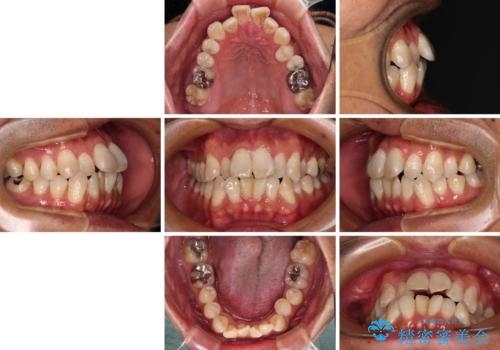

- 前歯のデコボコとクロスバイトを気にして来院された患者様です。

40代半ばであり、あまり周りに気を遣われずに治療を進めたいとのことで、インビザラインにて矯正治療を行うこととしました。

毎日22時間の装着時間をきっちりと守ってくださり、1年半かけずに思い通りの歯列に仕上げることができました。